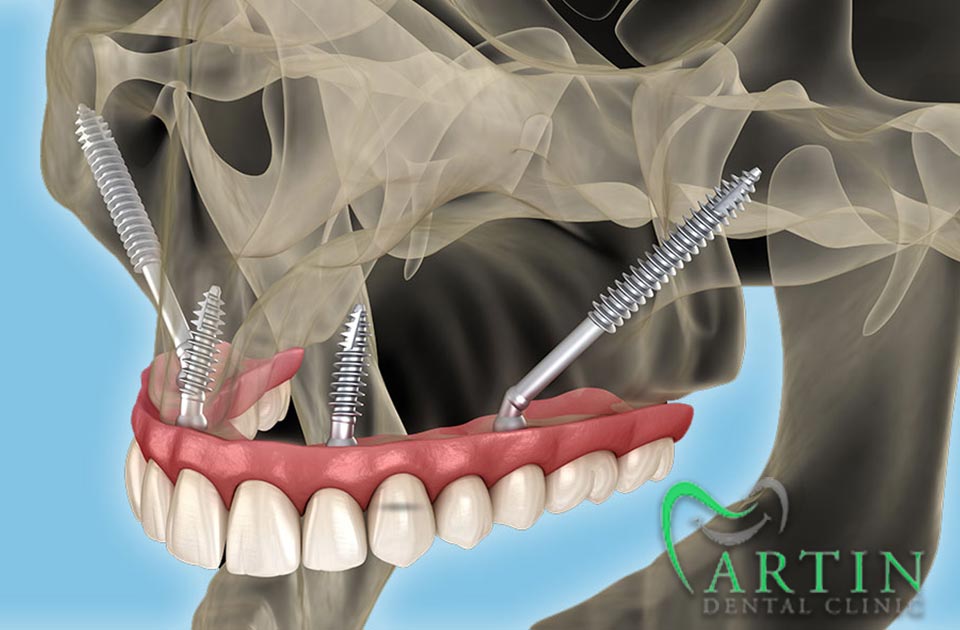

این نوع ایمپلنت به ویژه برای بیمارانی که دچار کمبود استخوان در فک هستند، طراحی شده و به استخوان زیگوماتیک (استخوان گونه) متصل میشود.

عمل جراحی

- بیحسی: استفاده از بیحسی موضعی یا عمومی برای راحتی بیمار در طول عمل.

- عمل جراحی: ایجاد برش در لثه و قرار دادن ایمپلنت در استخوان زیگوماتیک. این مرحله نیازمند دقت و مهارت بالای جراح است.

این نوع ایمپلنت به ویژه برای بیمارانی که استخوان فک کافی ندارند، یک گزینه قابل اعتماد به شمار میآید. با استفاده از استخوان زیگوماتیک، این نوع ایمپلنت میتواند به خوبی در دهان قرار گیرد و عملکرد بهتری ارائه دهد.

کاهش نیاز به پیوند استخوان